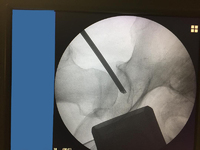

Κατά την αρθροσκόπηση του ισχίου ο Ορθοπαιδικός Χειρουργός εισάγει μία μικρή κάμερα που ονομάζεται αρθροσκόπιο στην άρθρωση του ισχίου με τον ασθενή σε ειδικό χειρουργικό τραπέζι όπου ασκείται έλξη του πάσχοντος άκρου. Η κάμερα εμφανίζει εικόνες σε μία οθόνη όπου ο χειρουργός χρησιμοποιεί αυτές τις εικόνες για να καθοδηγήσει μικροσκοπικά χειρουργικά εργαλεία με τα οποία πραγματοποιείται η διαγνωστική ή η θεραπευτική αντιμετώπιση της πάθησης του ισχίου. Επειδή το αρθροσκόπιο και τα χειρουργικά εργαλεία είναι λεπτά, ο χειρουργός μπορεί να χρησιμοποιήσει πολύ μικρές χειρουργικές τομές οι οποίες ονομάζονται αρθροσκοπικές πόρτες. Αυτό οδηγεί σε λιγότερο μετεγχειρητικό πόνο, λιγότερη δυσκαμψία της άρθρωσης και συχνά μειωμένο χρόνο αποκατάστασης. Είναι δηλαδή μια ελάχιστα επεμβατική τεχνική.